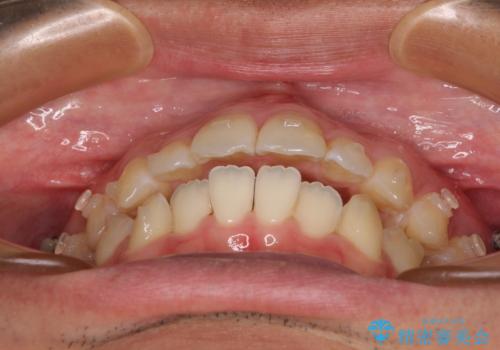

開咬とデコボコを整える インビザライン矯正治療

- 前歯の開咬と叢生を気にして来院された患者様です。

開咬の治療は、前歯を閉じるように動かすとともに、上下臼歯を圧下(骨内にめり込ませる)させることで進めて行きます。

インビザラインは臼歯の圧下を効果的に行えるため、インビザラインを用いて矯正治療を行うこととしました。また、アンカースクリューを用いて、口元の突出感の改善を図りました。